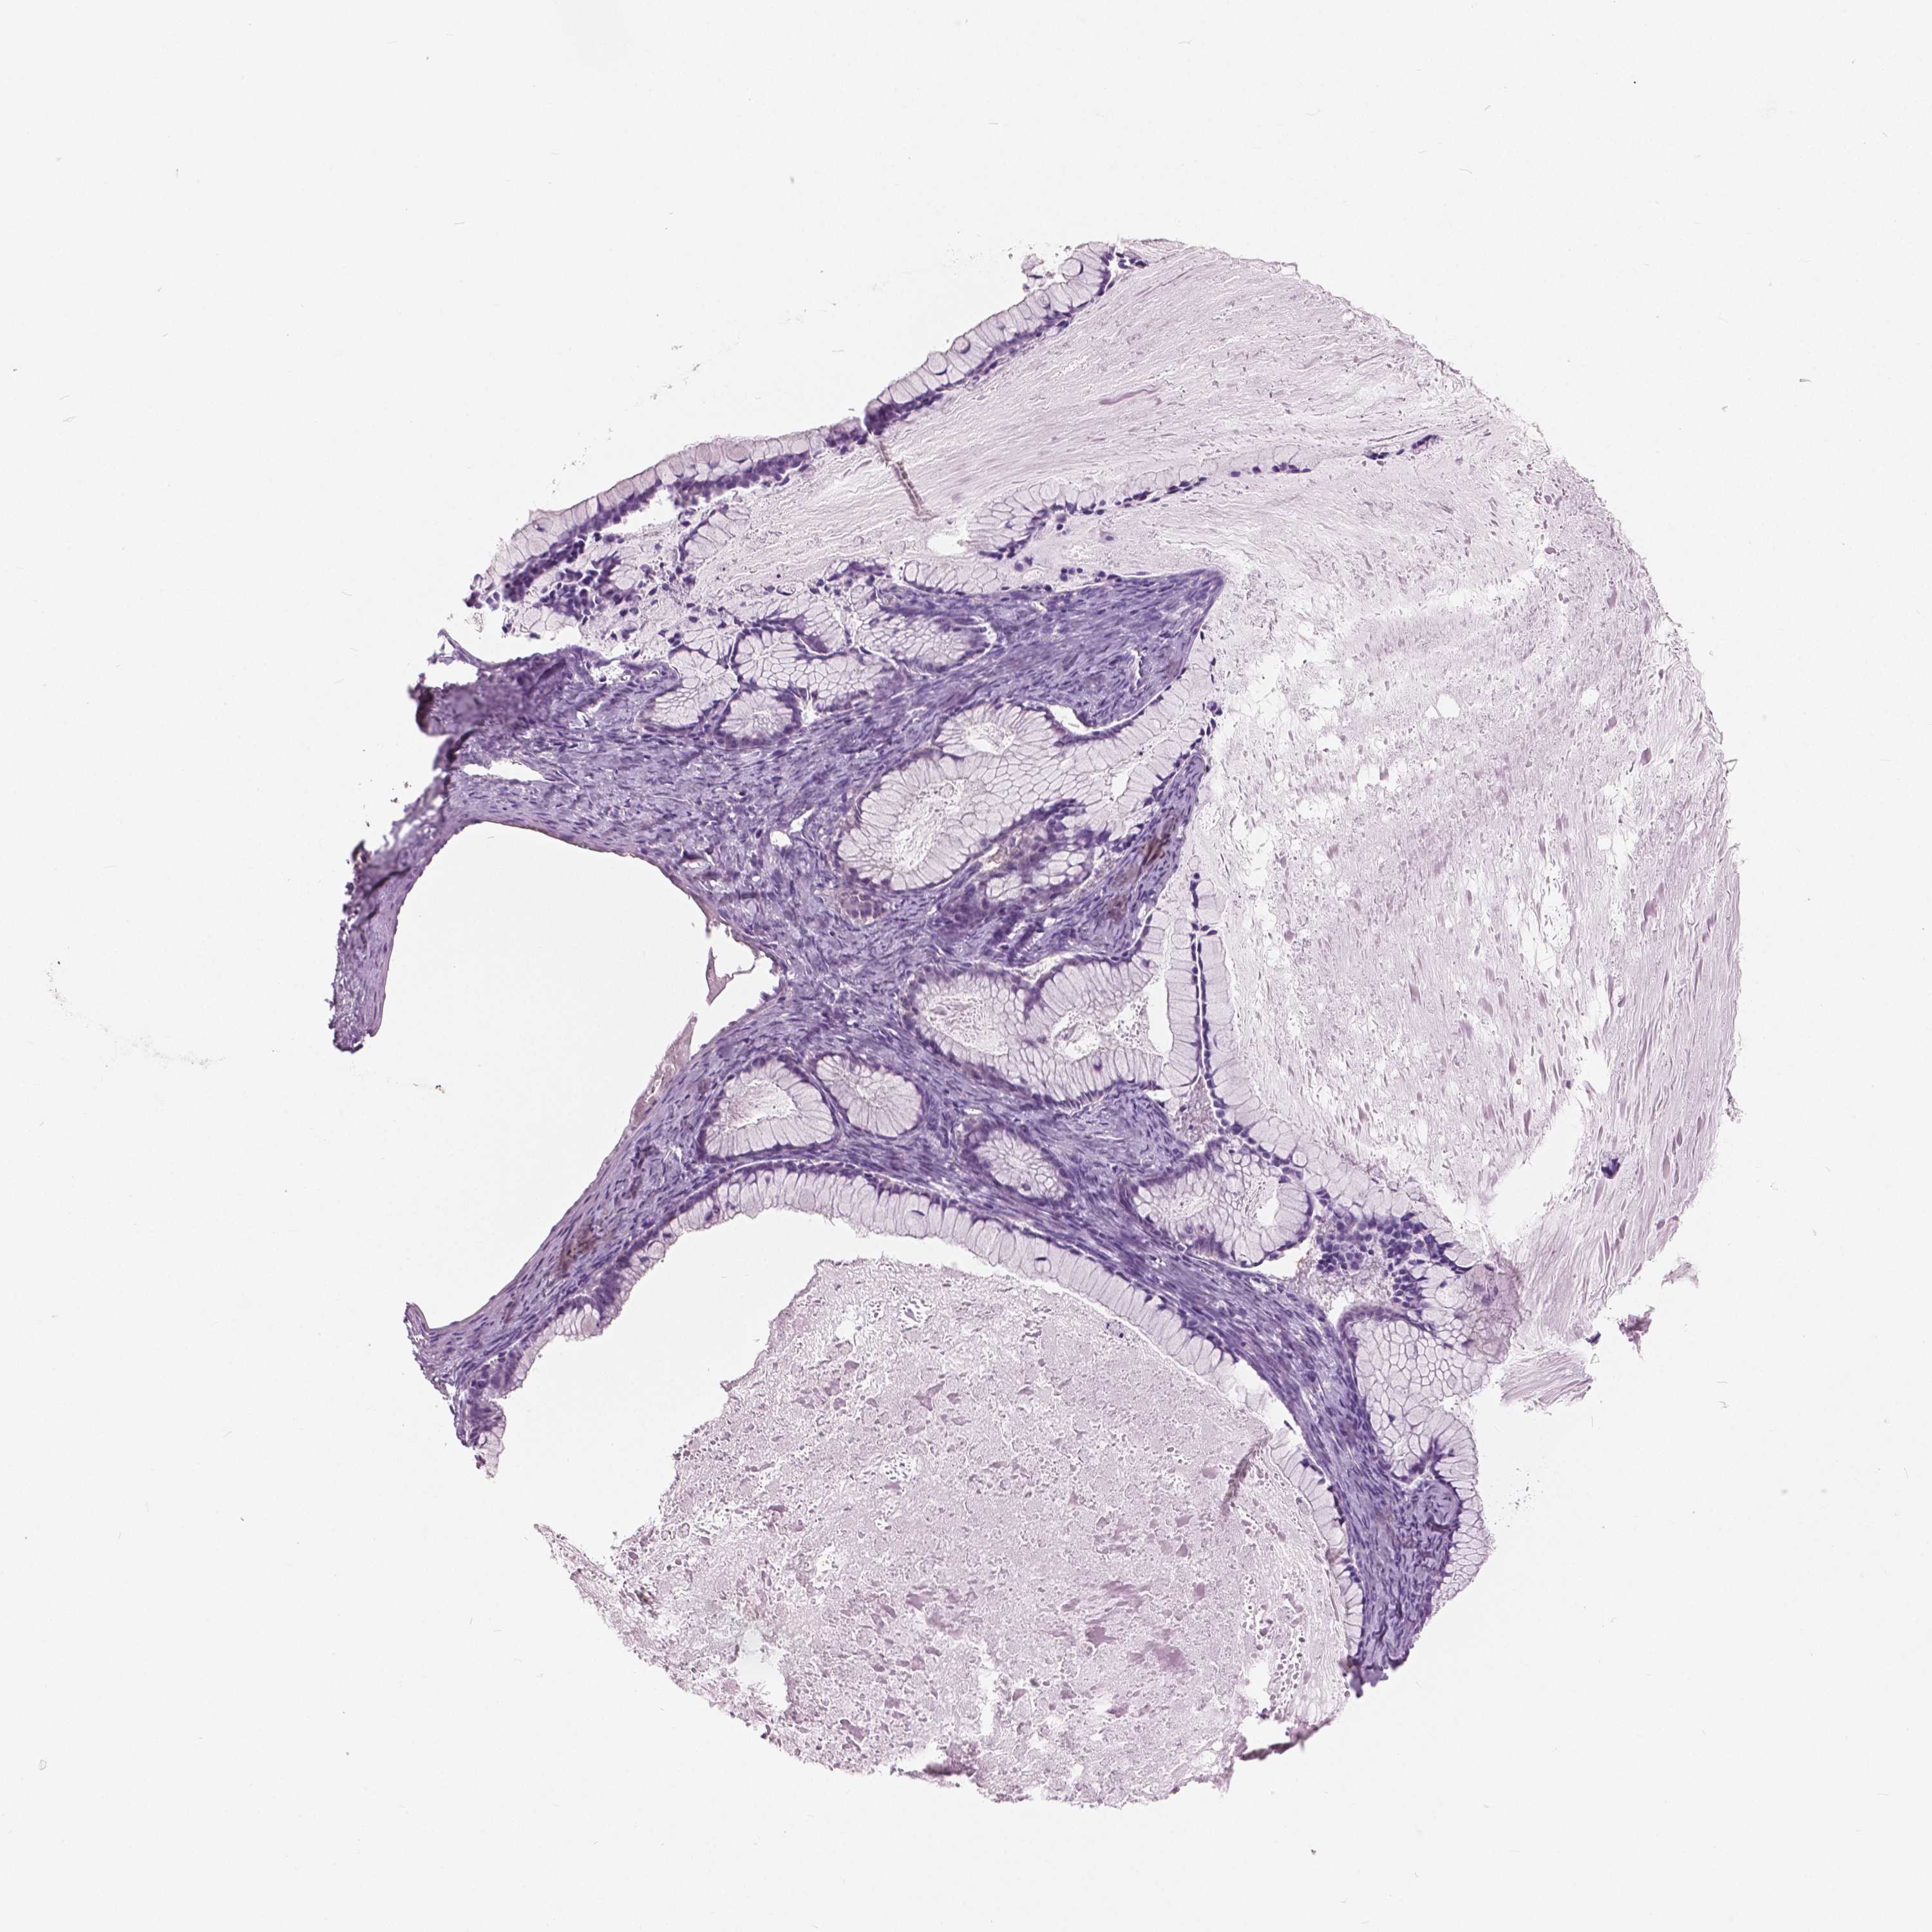

OVARIAN CANCER - Protein expressioni

A mouse-over function shows sample information and annotation data. Click on an image to view it in a full screen mode. Samples can be filtered based on level of antibody staining by selecting one or several of the following categories: high, medium, low and not detected. The assay and annotation is described here.

Note that samples used for immunohistochemistry by the Human Protein Atlas do not correspond to samples in the TCGA dataset.

Antibody stainingi

Antibody staining in the annotated cell types in the current human tissue is reported as not detected, low, medium, or high, based on conventional immunohistochemistry profiling in selected tissues. This score is based on the combination of the staining intensity and fraction of stained cells.

Each image is clickable and will lead to virtual microscopy that enables deeper exploration of all samples and also displays staining intensity scores, fraction scores and subcellular localization as well as patient and tissue information for each sample.

Antibody HPA035472

Antibody HPA035473

Antibody HPA064835

Cystadenocarcinoma, serous, NOS

Cystadenocarcinoma, mucinous, NOS

Carcinoma, endometroid